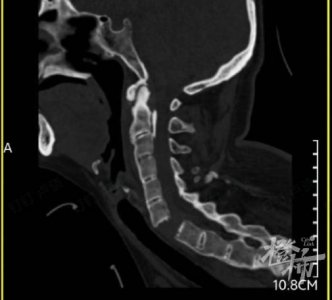

- 女子玩漂流颈椎骨折导致瘫痪

- 女子玩漂流颈椎骨折导致瘫痪 上周,50 岁的刘女士和亲友一起到富阳玩,坐皮划艇漂流时,突然发生意外。由于漂流时遇到高低落差,颠簸中刘女士颈椎受到冲撞挤压。 当时,刘女士...